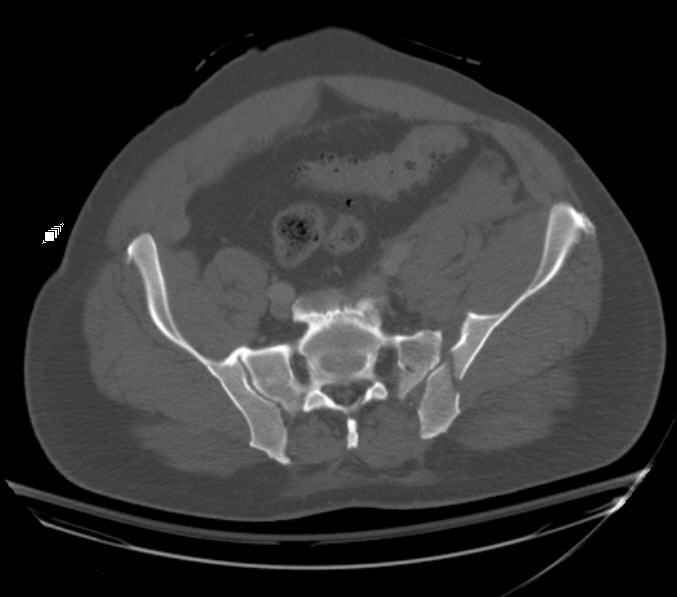

Re: APC III pelvis fx

Request for more images.. Axial and coronal recon (pt in binder.)

Haven't posted initial AP pelvis as it is poor quality, non digital film.